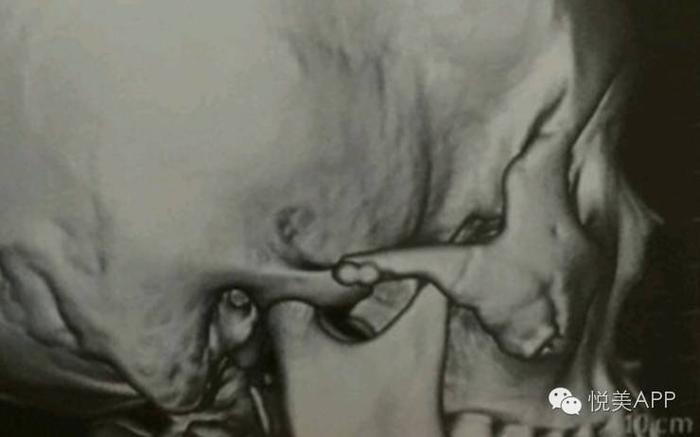

颧骨内推是有一定限度的,颧弓内推的极限决定于颧弓和下颌骨喙突之间的距离,颧弓内推只要不妨碍下颌骨喙突的运动,可以达到极限值。

下颌骨喙突位置:

也就是白色圆圈内的两块骨头距离,推太多会导致张口受限,影响功能

但咬肌的强大力量长期牵引,仍然造成了以下案例后端骨端的下滑,同时对前方的颧骨固定点形成了杠杆作用,强大的杠杆力使得前方固定点上端裂开。最终使颧弓向后下方旋转,翻转。

以下案例,后端未固定,只把整段骨块内移插入到后方骨端的内侧,但由于术后患者的咬肌运动,牵拉骨块,使得后段本来重叠推进去的骨端弹出,所以面部宽度最终未能缩小。

颧弓根部的截骨少量内推时,内推范围不超过颧弓根截面,要能接上才能骨性愈合。推多了后端骨头连不上,仅靠钛板固定,在咬肌牵拉下,单靠钛板钛钉固定仍然容易骨不连、下移、弹出。

后端的牵拉对前端造成杠杆效应,使得前方固定点上端裂开,最终使颧弓向后下方旋转,翻转。导致骨不连,骨块下移。